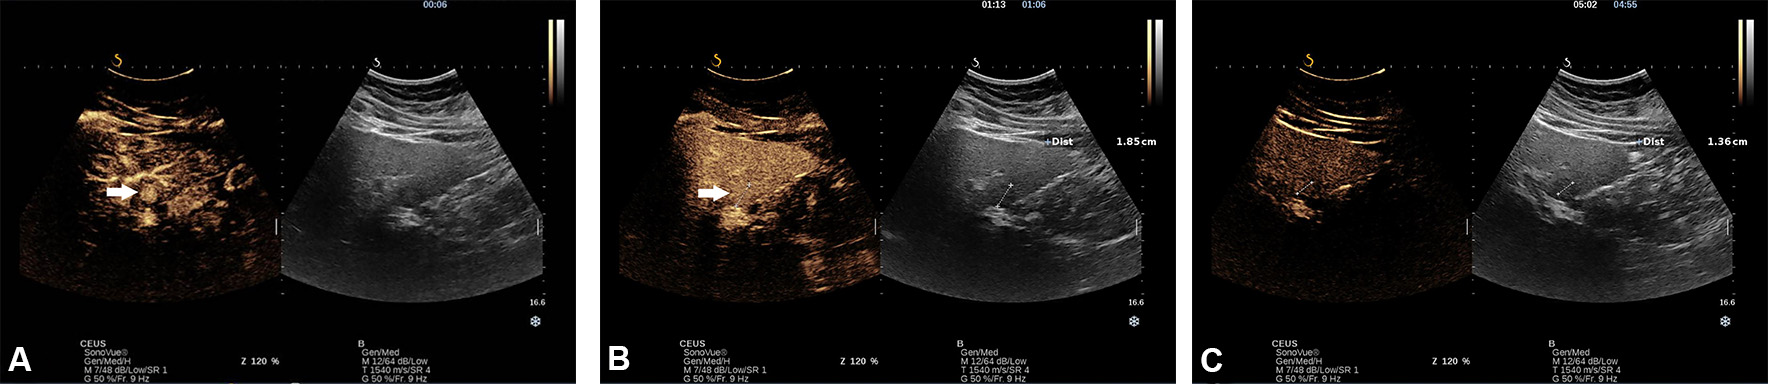

Based on the arterial enhancement pattern and presence/absence of washout phenomena in the portal venous and delayed phases, the lesion can be characterised by CEUS. As a general rule, the lack of washout during the portal venous and late phase indicates a benign lesion, in which case the arterial enhancement pattern indicates the type of lesion [Figure 5A-C].

Figure 5. Incidentally, hyperechoic lesion with a hypoechoic halo in a 23-year-old woman diagnosed with non-alcoholic liver steatosis. A CEUS with SonoVue was performed. In the early arterial phase, there was a rapid spoke-wheel enhancement of the lesion (arrows) from the centre to the periphery (A). In portal venous (B) and late phase, the lesion remained iso-enhanced compared with adjacent liver parenchyma, indicating that the lesion is benign (C).